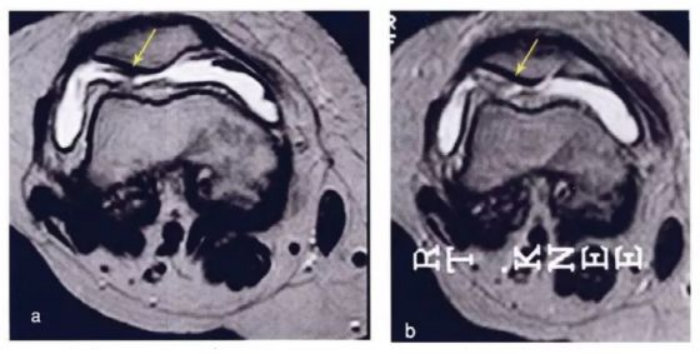

`研究结果:在ADSVF治疗后,,疼痛显著减轻,,,,没有发现不良反应。。

下图是治疗前后的核磁对比,,,,如之前的一样,,,,颜色越蓝,,代表软骨质量越好。。。。可以看出间充质干细胞治疗后软骨质量明显提高。。